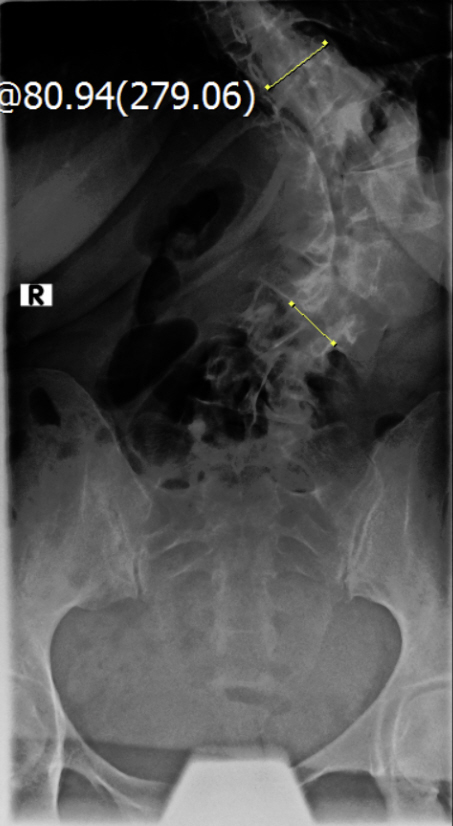

Diagnose: Thorakolumbalskoliose - Cobb-Winkel 60 und 80

Thorakolumbalskoliose mit aktuellen COBB-Winkeln von 80 und 60 Grad...wenig Schmerzen und daher meistens glücklich :D .

Viele kennen sich aus, daher möchte ich euch meine aktuellen Röntgenbilder nicht vorenthalten und hänge sie unten an.

Ich war beim MVZ Gersthofen, dort wurden die Röntgenbilder gemacht…die massive Verschlechterung war sehr offensichtlich :( , drum wurde ich gleich an die Experten zur Hessing Klinik überwiesen.

Dort wurden die Winkel gemessen, unten 80 Grad und oben 60 Grad…eine Verschlechterung von über 2 Grad pro Jahr, wenn man es auf die ganze Zeit berechnet :( .

2021-09-09_Unten_von_Vorne.jpg

(128.2 KiB) Noch nie heruntergeladen

Die Winkel hab ich nachgemessen, wie der Arzt der Hessing und hier mal als Screenshot

2021-09-09_messung_winkel_2unten.jpg

(124.8 KiB) Noch nie heruntergeladen